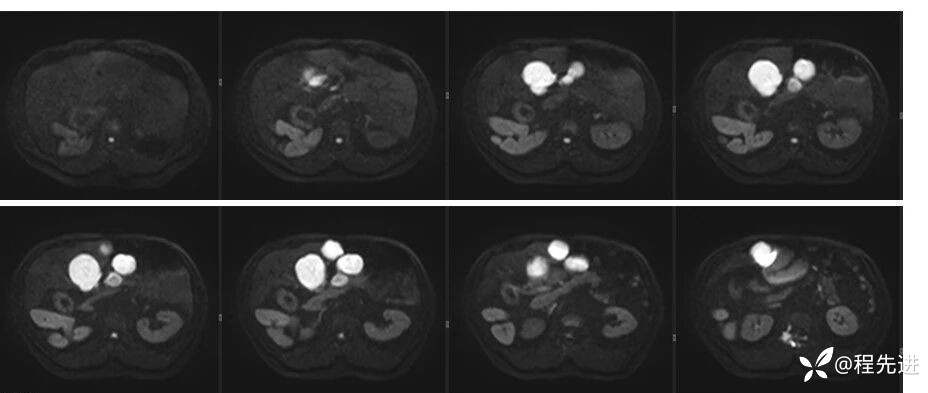

辅助检查:上腹部平扫+增强扫描提示:肝脏、脾脏、胰腺 、胃十二指肠左右倒置,脾脏形态失常,呈分叶团块状,考虑发育变异。肝左右交界区多发肿块,考虑:上皮样血管内皮瘤可能性大,或转移瘤?其它?请结合临床。脂肪肝。肝门胆管局限性扩张。胆囊折叠,壁稍增厚,慢性炎症?胰腺下方椭圆形结节,副脾?

影像检查